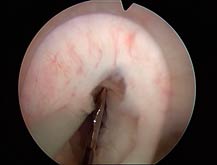

- Uretrotomia interna: um tipo especial de material denominado uretrótomo é introduzido pela uretra até o local da estenose. Uma pequena lâmina embutida corta o tecido fibrótico em toda a sua extensão, reestabelecendo a luz da uretra. Cerca de 30% dos pacientes apresenta cura. Alguns devem ser novamente submetidos ao procedimento pela recorrência na formação do tecido cicatricial. Trata-se de um método atraente por ser realizado de maneira endoscópica, minimamente invasiva, sendo mais indicado para estenoses curtas (< 1.5 cm).

Imagens endoscópicas de procedimento de uretrotomia interna, desde a estenose até a sua resolução